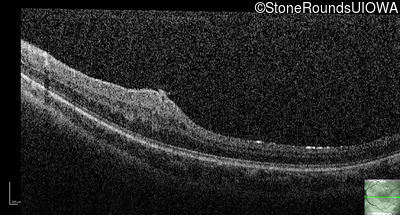

This 9 year old male was noted to have some crossing of his eyes at 2 months of age and the eye exam which followed identified a retinal lesion in the right eye. When he was six years old an epiretinal membrane was noted in his left eye. Two years later it was decided that it was a thin hamartoma in that eye as well. He underwent neuroimaging at age 7 which identified bilateral acoustic neuromas.

| Age at visit: 8 years |

| Age at visit: 10 years |